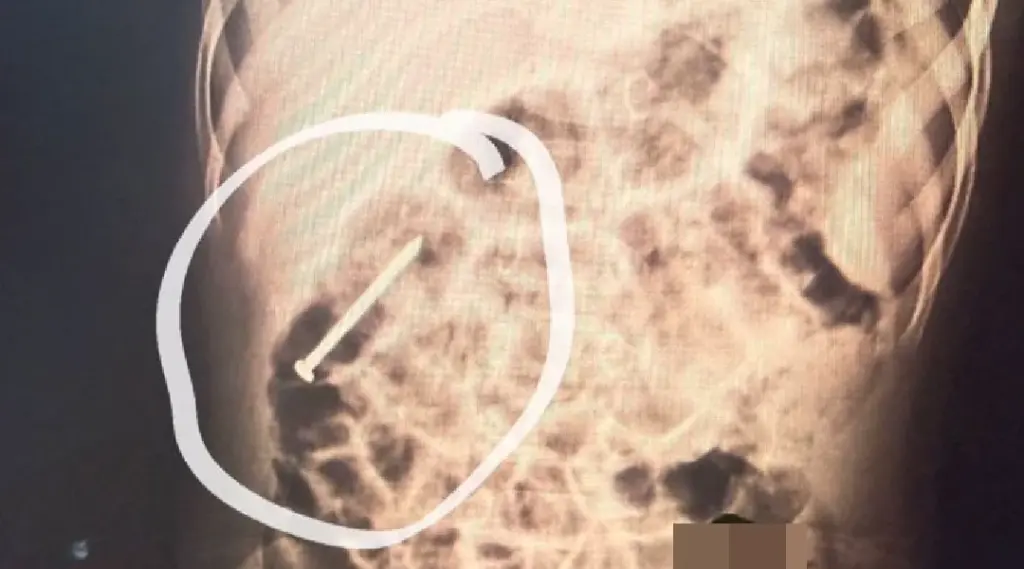

Um menino de dois anos, residente no município de Ipixuna, permanece internado no Hospital do Juruá após ingerir um prego há aproximadamente seis dias. Desde a admissão, a criança está sob observação da equipe médica da unidade.

Segundo os profissionais de saúde, o objeto metálico vem se deslocando pelo sistema digestivo de forma espontânea. Como medida preventiva, o paciente segue hospitalizado para acompanhamento contínuo, enquanto se aguarda que o material seja eliminado naturalmente, sem necessidade de procedimento invasivo.

Até o momento, o quadro clínico do menino é considerado estável. A equipe médica realiza exames periódicos e mantém vigilância constante para assegurar que não surjam complicações durante a evolução do caso.